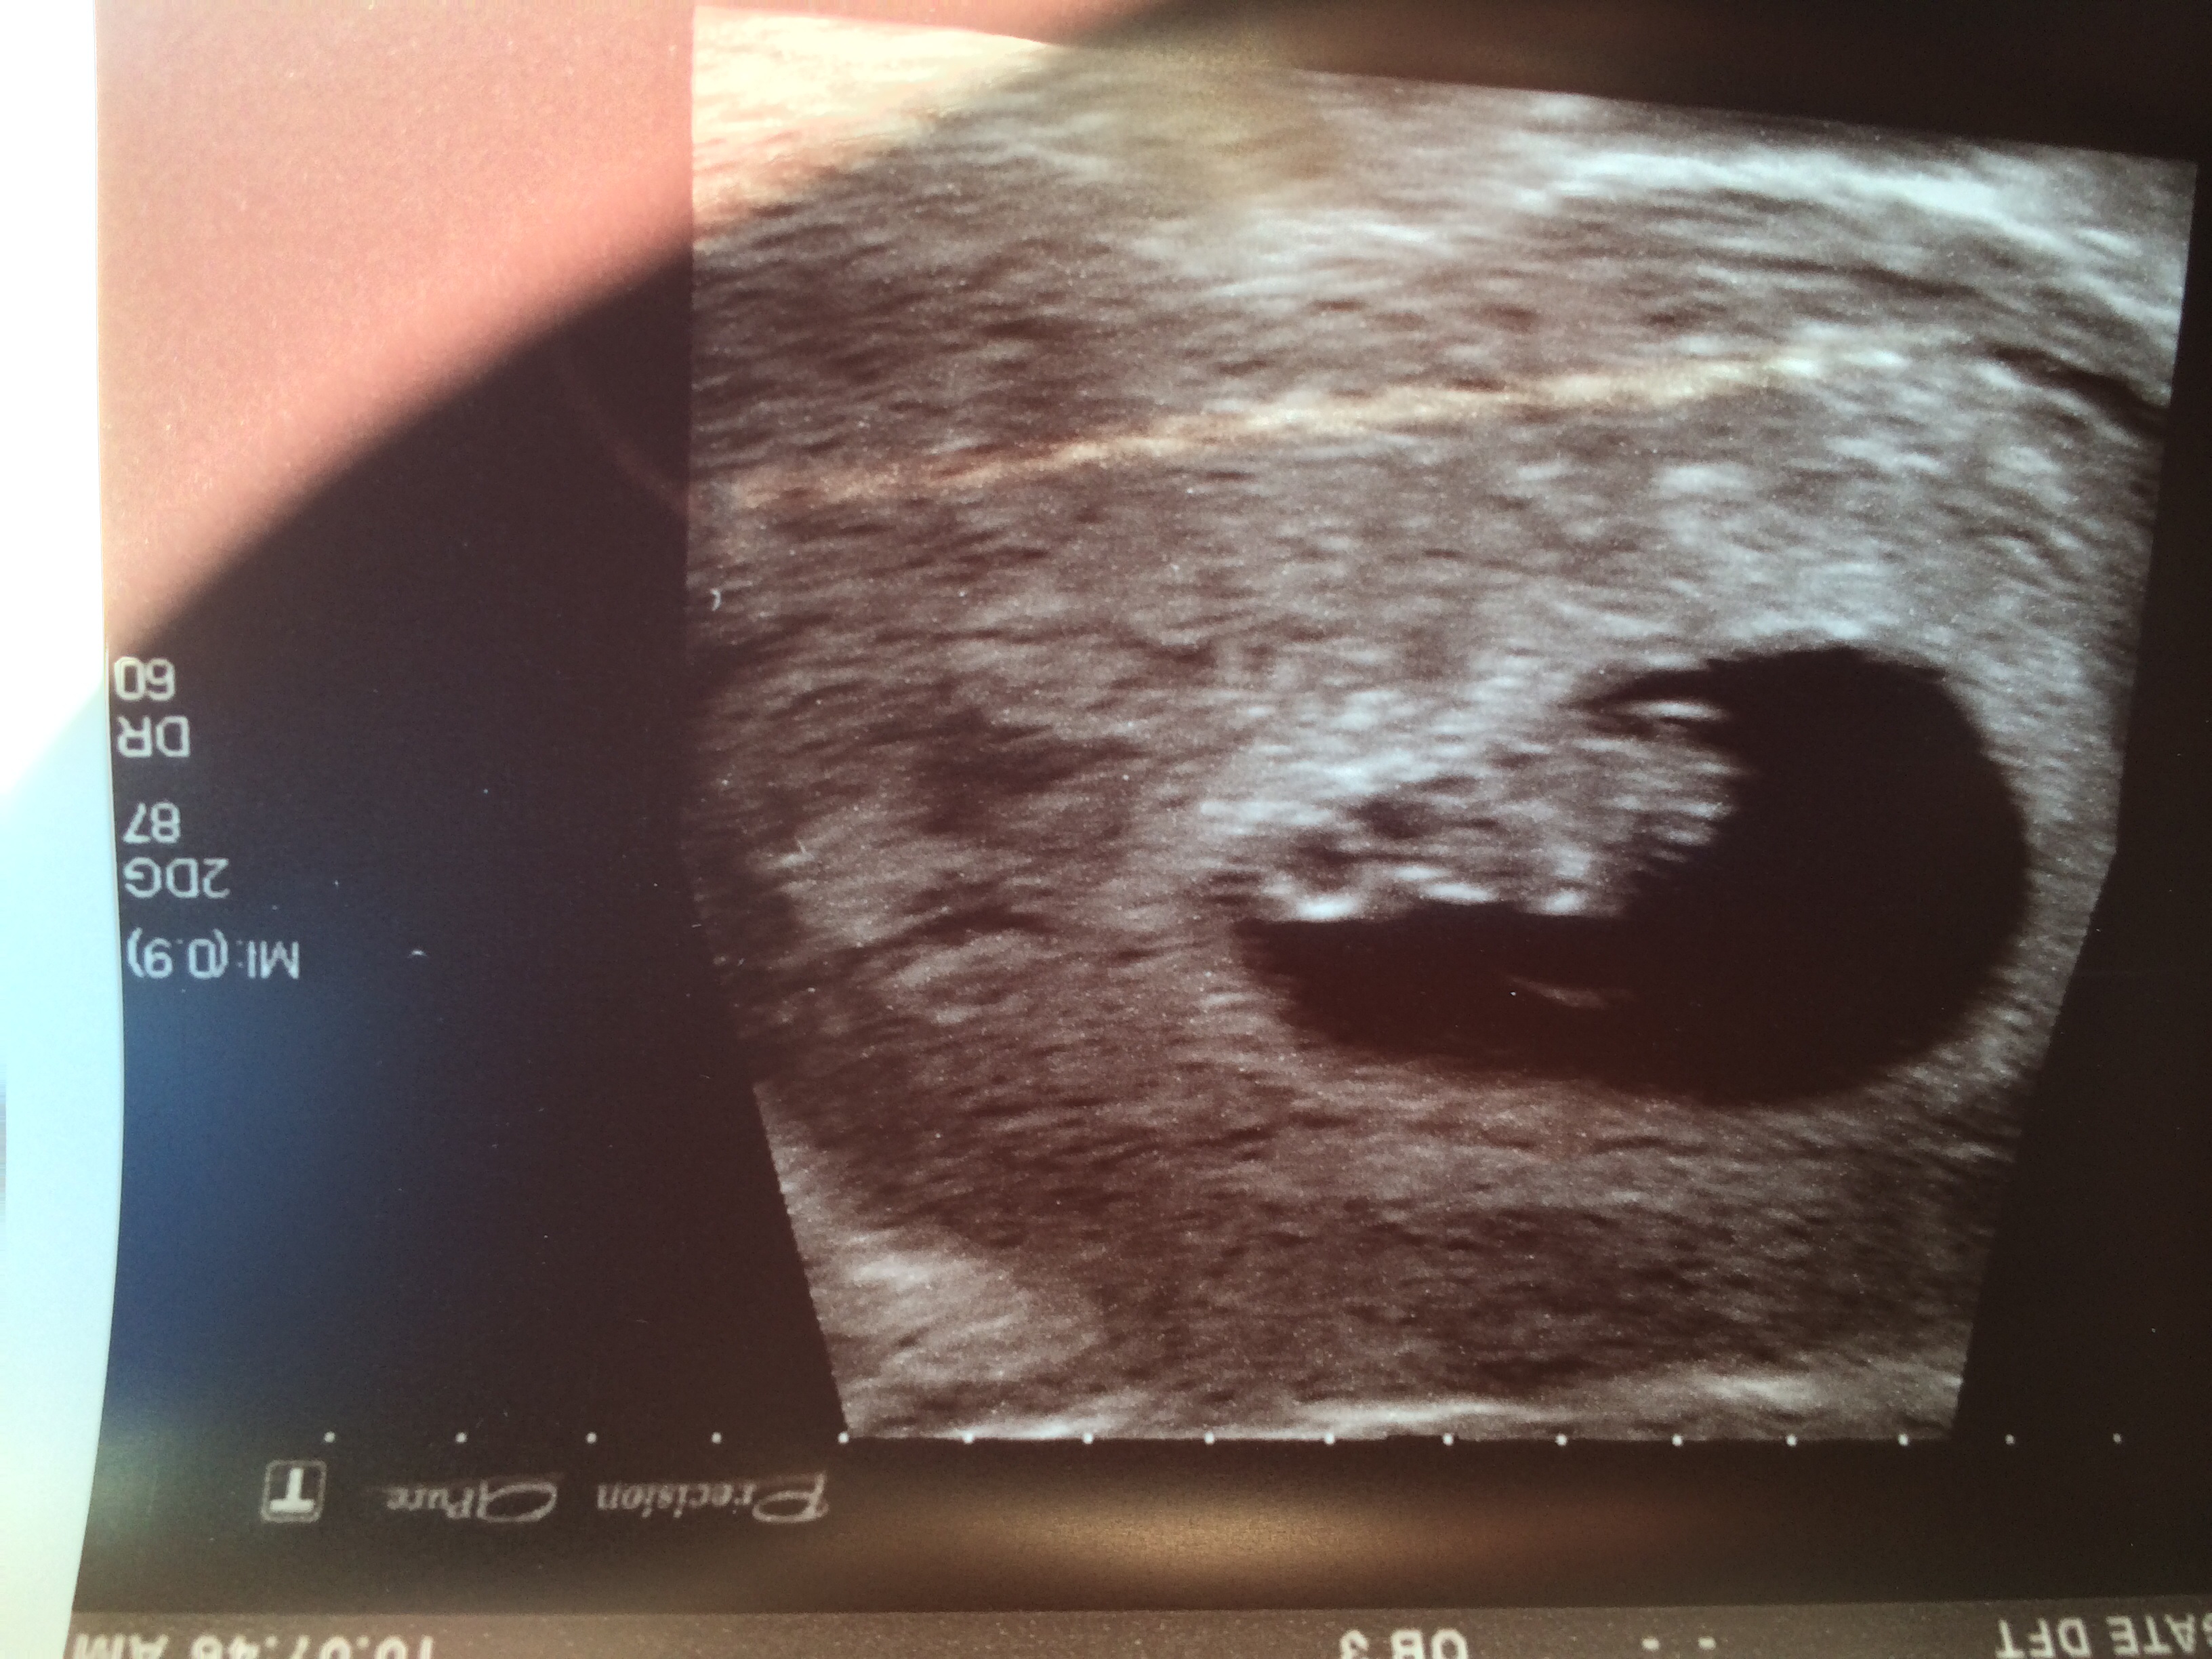

First pic is at 7+6, second two are today at 12+5 - don't think I see a nub, but any guesses are very welcome!! TIA ladies :)

I (Personally) don't see a nub, but what a cute baby! Good Luck!

No nub, but beautiful baby!!